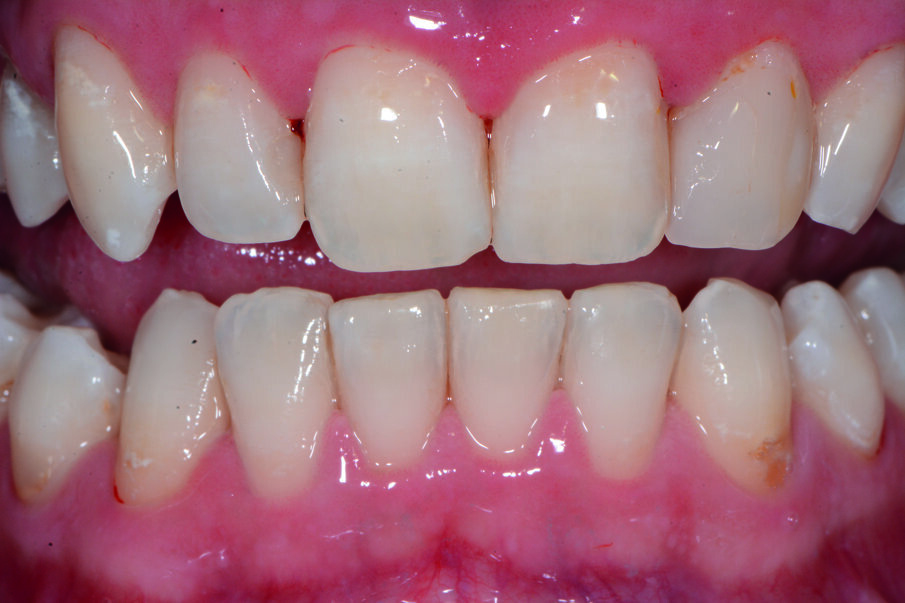

Durante l’esame obiettivo (Figg. 1a, 1b) rileviamo il danno iatrogeno da terapia ortodontica precedente alla visita e riscontriamo la presenza di processo carioso ICDAS 3 in zona 33 e in zona 47, white spots in zona 31 e 41. Durante l’esame obiettivo, l’ausilio della videocamera intraorale Sopro-Care (Acteon) permette, tramite filtri appositi, di evidenziare in modo rapido e accurato le zone di demineralizzazione e le aree infiammate e di mostrarle al paziente in real time, rendendolo attivamente partecipe e consapevole della situazione clinica (Figg. 2a-2f). I ricercatori del Baylor College of Dentistry hanno dimostrato che il 23,4% dei pazienti ha sviluppato almeno una white spot lesion durante il trattamento ortodontico.

Chiediamo al paziente se si fosse sottoposto a terapia ortodontica e il paziente riferisce di essersi sottoposto a terapia ortodontica in età adolescenziale per circa 2 anni e di non aver dato molta importanza alle lesioni presenti, poiché non aveva avuto grande sintomatologia riteneva che le white spots presenti non fossero un segno di demineralizzazione. Alla domanda della causa delle lesioni riferiamo che un inefficace controllo di placca domiciliare e uno stile di vita alimentare cariogeno, alzava il rischio di demineralizzazione delle lesioni che probabilmente erano state provocate dall’apposizione delle bande ortodontiche con materiale non di ultima generazione come i cementi vetroionomerici in grado di liberare fluoro. Inoltre riferiamo che durante la fase terminale del debonding, la topografia delle lesioni faceva presupporre l’uso poco attento di frese che avevano danneggiato lo smalto. Il paziente si mostra motivato e chiede una soluzione terapeutica che abbia come obiettivo la risoluzione funzionale ed estetica più veloce possibile. Viene condiviso con il paziente il piano terapeutico e proponiamo di iniziare con la terapia parodontale non chirurgica. Concordiamo con il paziente tempi, modalità di utilizzo e strumenti per migliorare il management degli stili di vita domiciliari, per il controllo chimico e meccanico del biofilm batterico (Nardi GM, Sabatini S, Guerra F, Tatullo M, Ottolenghi L. Tailored Brushing Method (TBM): an innovative simple protocol to improve the oral care. J Bio- med 2016; 1:26-31).